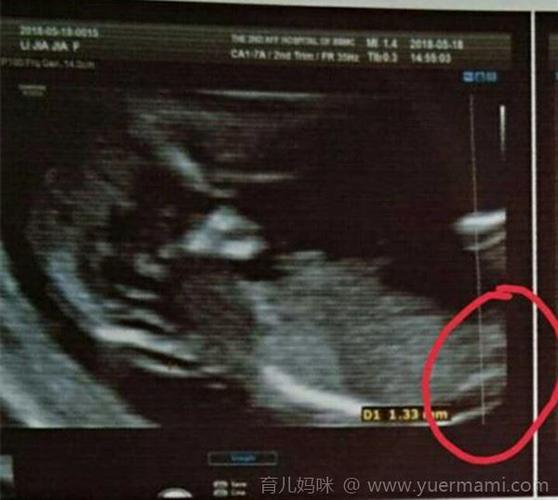

nt看男孩女孩诀窍,nt值看男孩女孩诀窍

11周 6 nt顺利归来,猜男孩女孩

nt可以看出男孩还是女孩吗

感觉是男孩还是女孩呢 我的nt

nt男孩b超图

怀男孩nt图片

怀女孩的nt图片

怀男孩nt报告图片

nt男女图对照表

13周nt图弯着就是男孩

nt照平躺的是女孩图